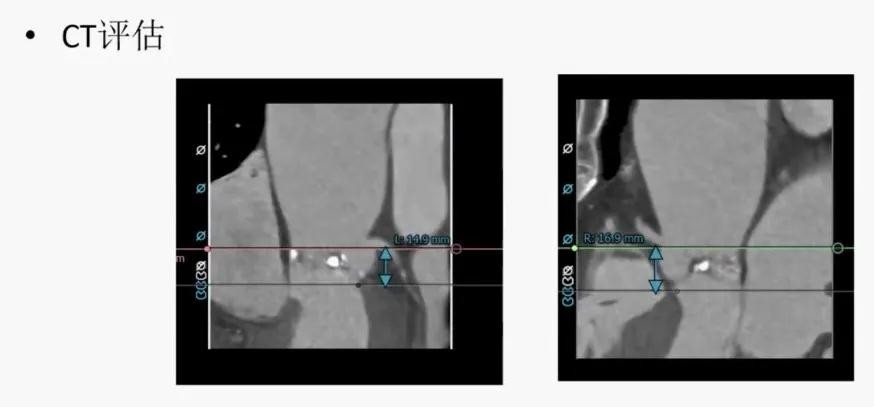

TAVR CT评估:主动脉瓣二瓣化畸形,TYPE 1型,左右窦融合;瓣叶中重度钙化;升主动脉瘤样扩张;冠状动脉未见明显狭窄病变,左右冠开口较高,无冠脉阻塞风险;双侧股动脉迂曲,直径尚可。手术选择右侧股动脉20F鞘管主入路,根据瓣环和瓣上结构,预估选择26mm或29mm Venus A-Valve(杭州启明)。术中23mm Numed球囊预扩,通过balloon sizing确定瓣膜直径。

CT外周路径评估